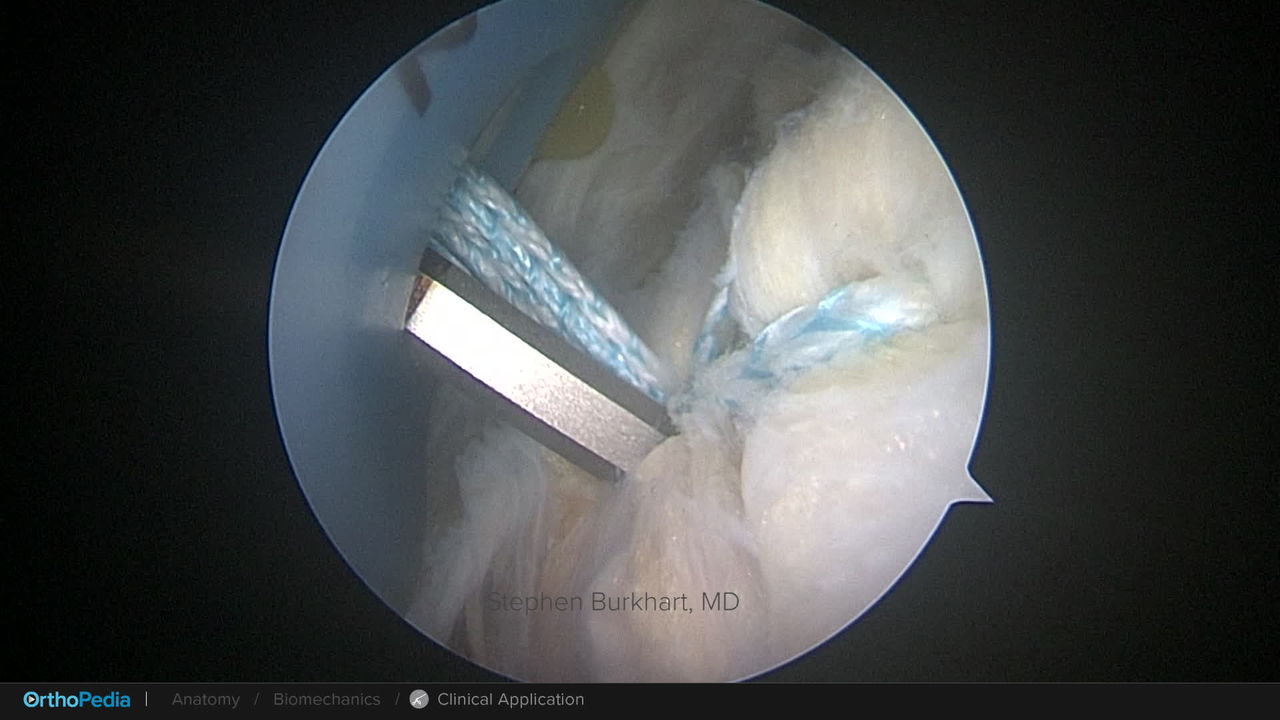

Posterosuperior Rotator Cuff Tears: Knotless Double-Row Repair With SpeedBridge™ Technique and SwiveLock® Anchors

Posterosuperior Rotator Cuff Tears: PASTA Bridge Technique With Knotless Corkscrew® Suture Anchor and SwiveLock® Anchors

Posterosuperior Rotator Cuff Tears: SpeedFix™ Knotless Single-Row Rotator Cuff Repair Single Row Repair With a SwiveLock® Anchors

Posterosuperior Rotator Cuff Tears: Knotless Double-Row Repair With SpeedBridge™ Technique and FiberTak® Soft Anchors

Proximal Biceps Tendinopathy: Arthroscopic High-Groove Tenodesis Technique With Loop 'N' Tack Technique